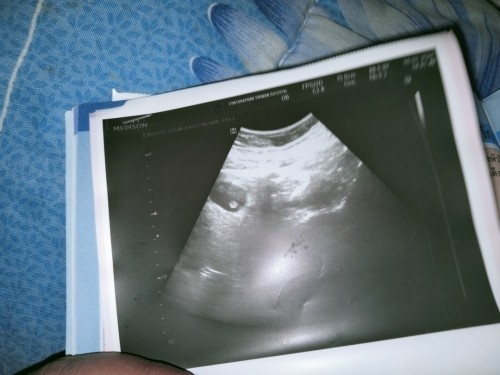

เคยฝังยาคุมกำเนิดมา5ปี ไม่เป็นประจำเดือนเลยค่ะ พึ่งถอดเมื่อวันที่11มีนา64 วันที่11-12/20-21-22เมษา64 มีเลือดคล้ายประจำเดือนมา4-5หยด คิดว่าตัวเองท้องแต่ตรวจไม่เจอจนมาวันที่28พฤษภา64ตรวจเจอการตั้งครรภ์ แต่ไม่รู้ว่ากี่สัปดาห์ ตามใบซาวหมอบอกคนที่1บอก6w+6d ใบซาวใบที่2หมอคนที่2บอก12w+3d ไปไม่ถูกเลยค่ะ วงกลมๆในถุงใช้ลูกมั้ยคะ เครียดมากเลยค่ะตอนนี้ หมอก็ยังบอกไม่ได้ว่ากี่สัปดาห์

เบบี๋น้อย